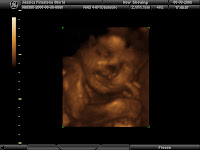

Our baby at 30 weeks!

We had a 3-D ultrasound done yesterday and the baby was sleeping the whole time :) He loves his daddy- he moved every time he heard his voice :) We got some pretty cute pics! We can't wait to see him in person- He is perfect!!